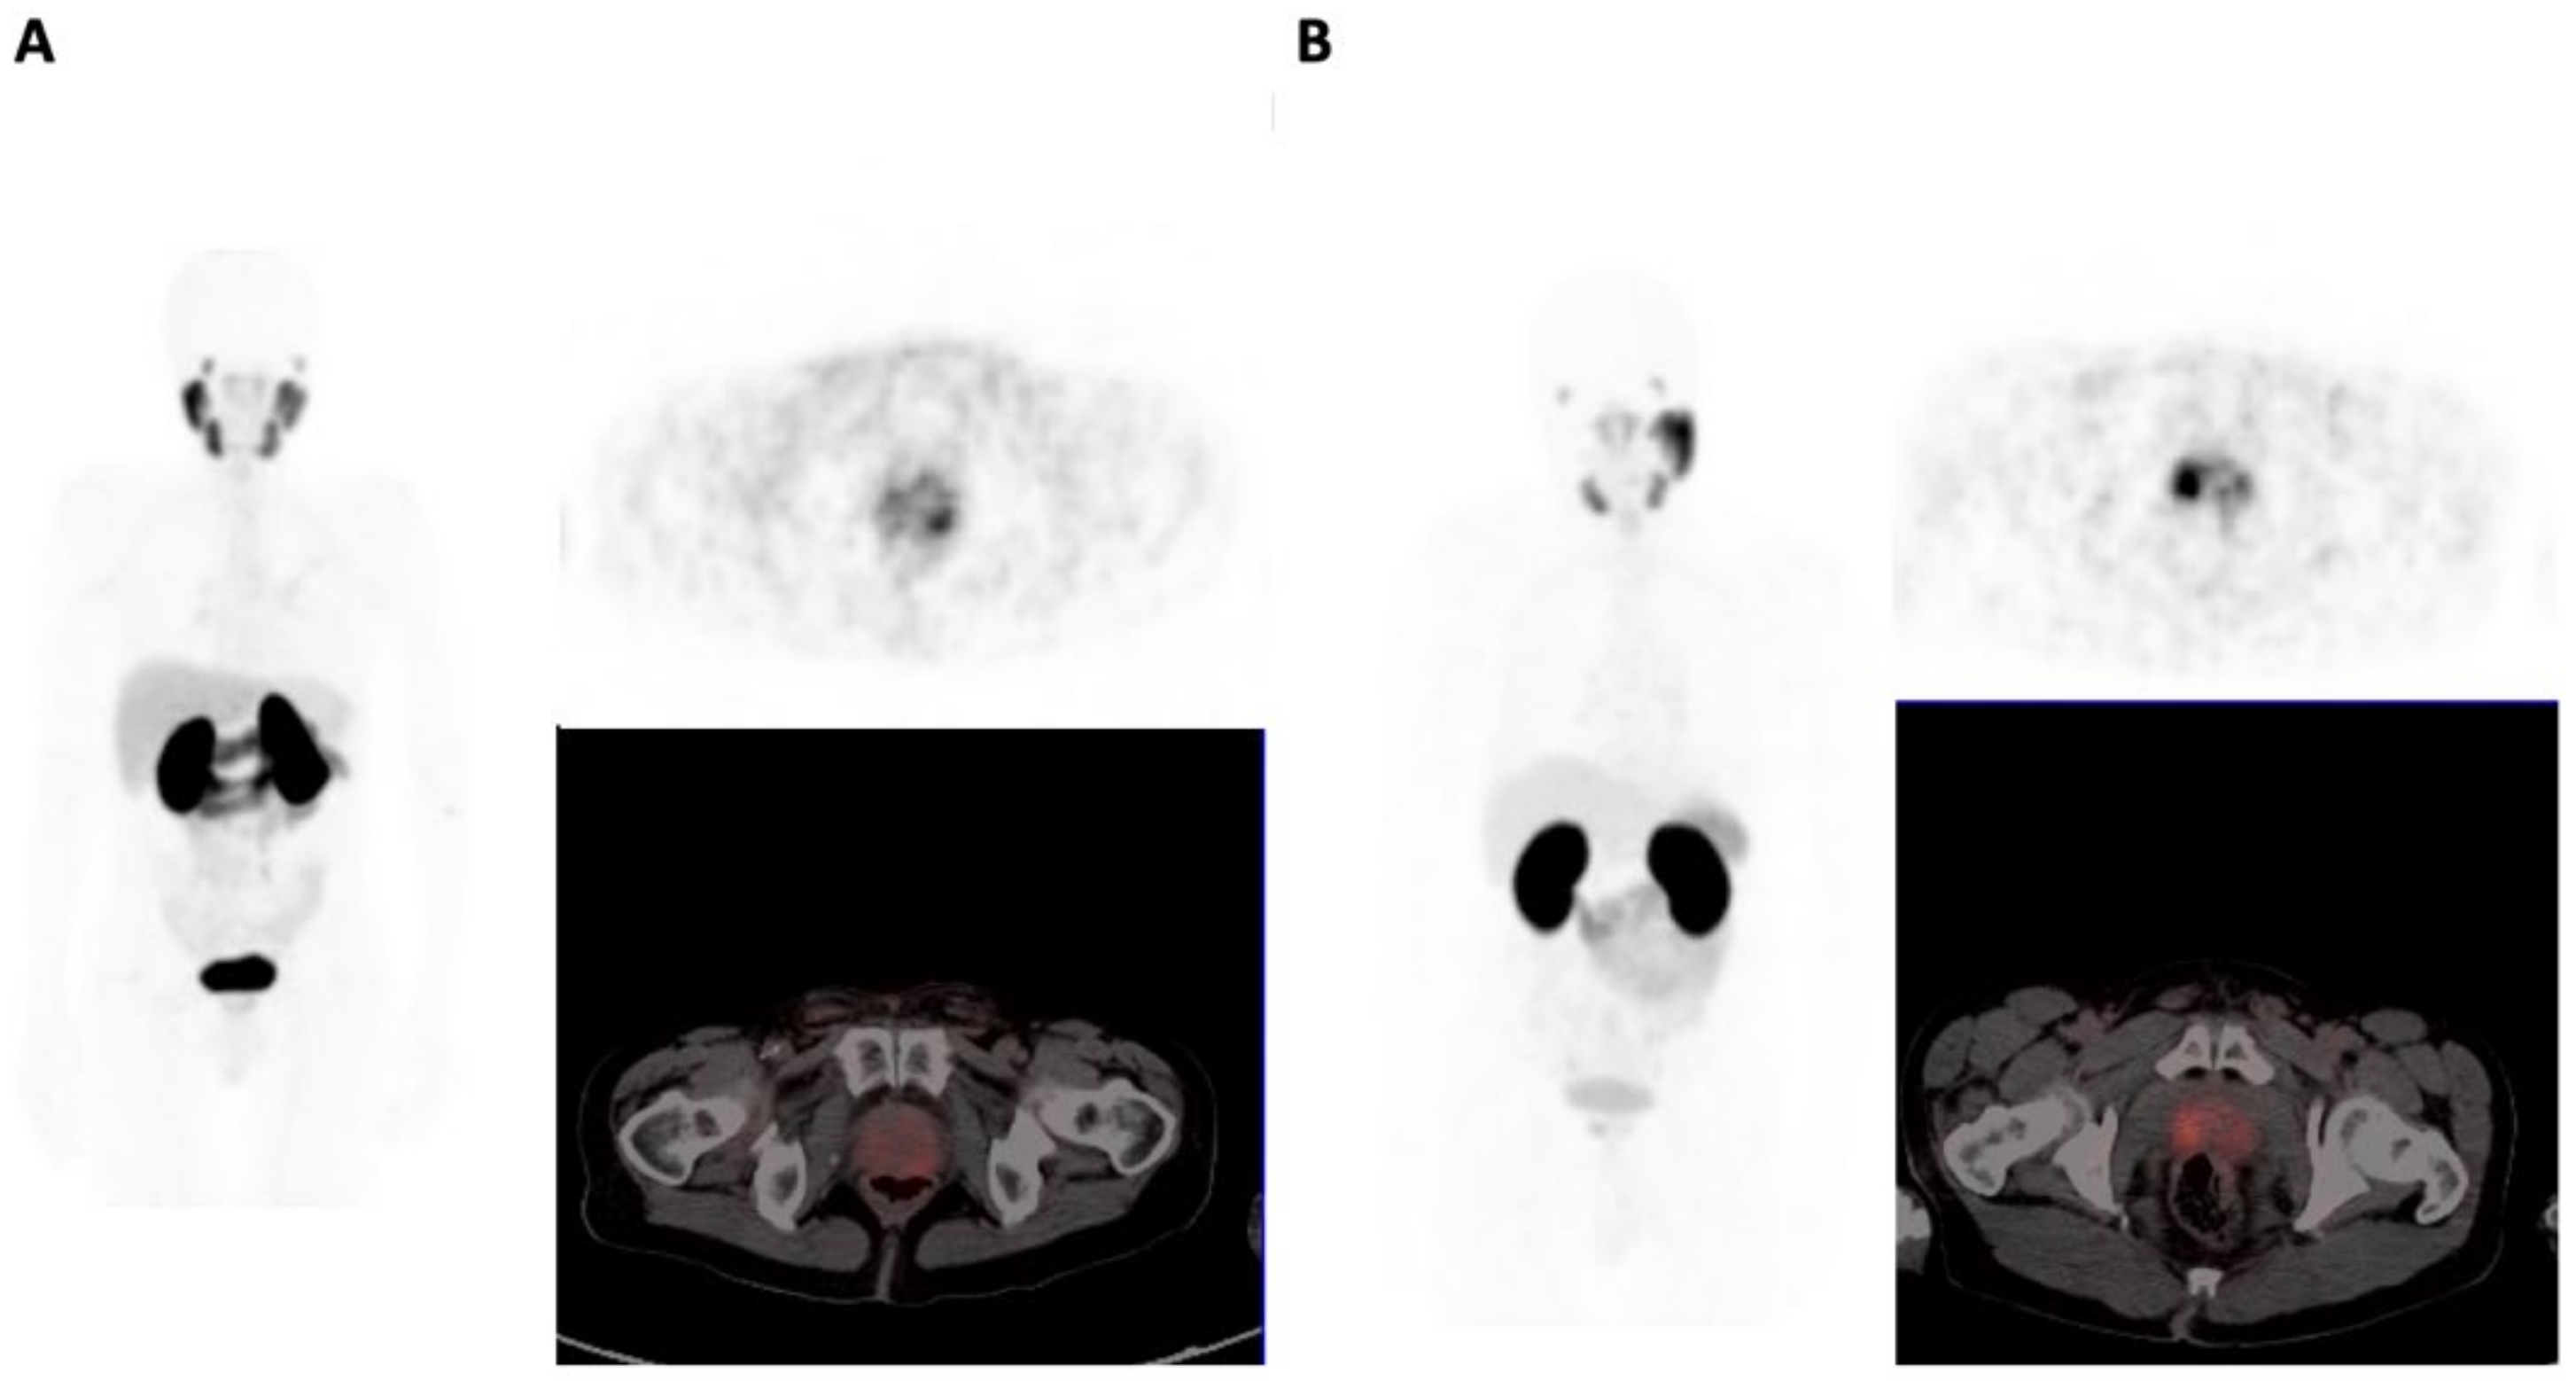

3.2. 68Ga-PSMA PET/CT Analysis

3.3. Comparison of BSA and WSA Males

3.3.1. Primary Tumor

3.3.2. Metastatic Involvement